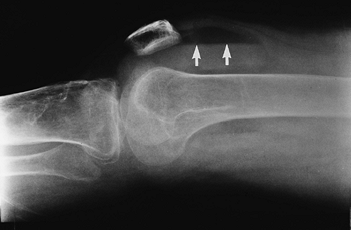

P.229

FIGURE 5-16 Cross-table lateral radiograph demonstrating a lipohemarthrosis (arrows) indicating an intra-articular fracture.